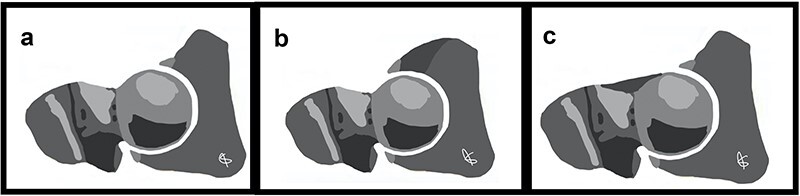

股髋臼撞击综合征(FAIS)是髋关节的一种常见疾病,可对关节造成严重损害,导致退变和骨关节炎。FAIS是股骨头颈交界处与髋臼缘之间的异常动态接触,由一个或两个部位的骨形态改变引起。撞击部位的重复性创伤会对髋臼唇、软骨唇交界处和关节软骨造成进行性损伤。基于患者症状、特定临床体征和影像学表现的正确诊断将指导治疗并最终保留原有髋关节。FAIS患者的常见症状包括疼痛、咔嗒声、卡住、屈曲、僵硬、让位和髋关节活动范围有限。具体的临床操作可以帮助诊断,如屈曲内收内旋和屈曲外展外旋试验。影像学诊断包括髋关节和骨盆的正交x线片,以及磁共振成像/磁共振关节成像。FAIS的初始治疗可以是保守治疗,包括物理治疗、关节内注射和活动调节。目前,首选的手术治疗包括髋关节镜检查,其目的是纠正骨骼异常,修复或重建唇部病变,并根据需要处理其他关节内和关节外的紊乱。

Femoroacetabular impingement syndrome (FAIS) is a common condition of the hip that can cause significant damage to the joint, leading to degeneration and osteoarthritis. FAIS constitutes an abnormal and dynamic contact between the femoral head-neck junction and the acetabular rim, resulting from altered bone morphology at one or both sites. Repetitive trauma at the site of impingement generates progressive damage to the acetabular labrum, chondrolabral junction, and articular cartilage. Proper diagnosis based on patient symptoms, specific clinical signs, and imaging findings will guide treatment and ultimately allow preservation of the native hip joint. Common symptoms in patients with FAIS include pain, clicking, catching, buckling, stiffness, giving way, and a limited range of motion of the hip. Specific clinical maneuvers can aid diagnosis, such as flexion adduction internal rotation and flexion abduction external rotation tests. Imaging diagnosis includes orthogonal hip and pelvis X-ray views, as well as magnetic resonance imaging/magnetic resonance arthrogram imaging. Initial treatment of FAIS can be conservative and include physical therapy, intra-articular injections, and activity modification. Currently, the preferred surgical management consists of hip arthroscopy, which aims to correct bony abnormalities, repair or reconstruct labral lesions and address other intra-articular and extra-articular derangements as needed.